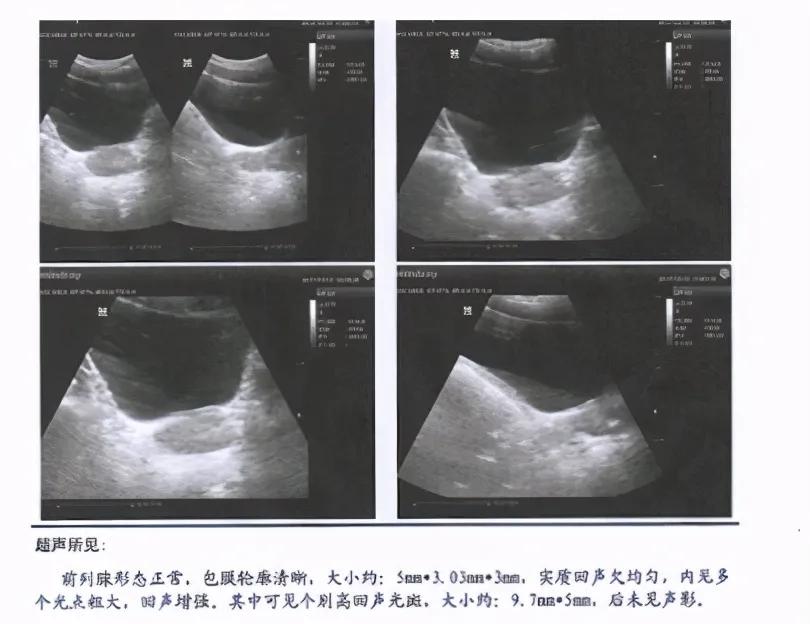

他的B超检查可见前列腺形态正常,包膜轮廓清晰,大小约:50*30*30mm,实质回声欠均匀,内见多个光斑粗大,回声增强。

其中可见1个高回声光斑,大小约:9.7*5mm。

他的前列腺既有功能上的损伤,又有器质性的病变。

综合了患者所有资料,可以确诊患者患的是前列腺增生伴钙化。

患者的前列腺病变比较严重,有多处病灶,所以腺体增生也比较严重。